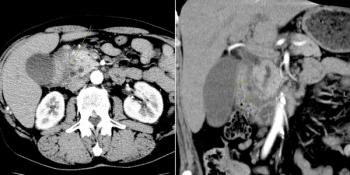

A 52-year-old man with a history of heavy alcohol use and chronic abdominal pain presents with the following CT scan. What is your diagnosis?